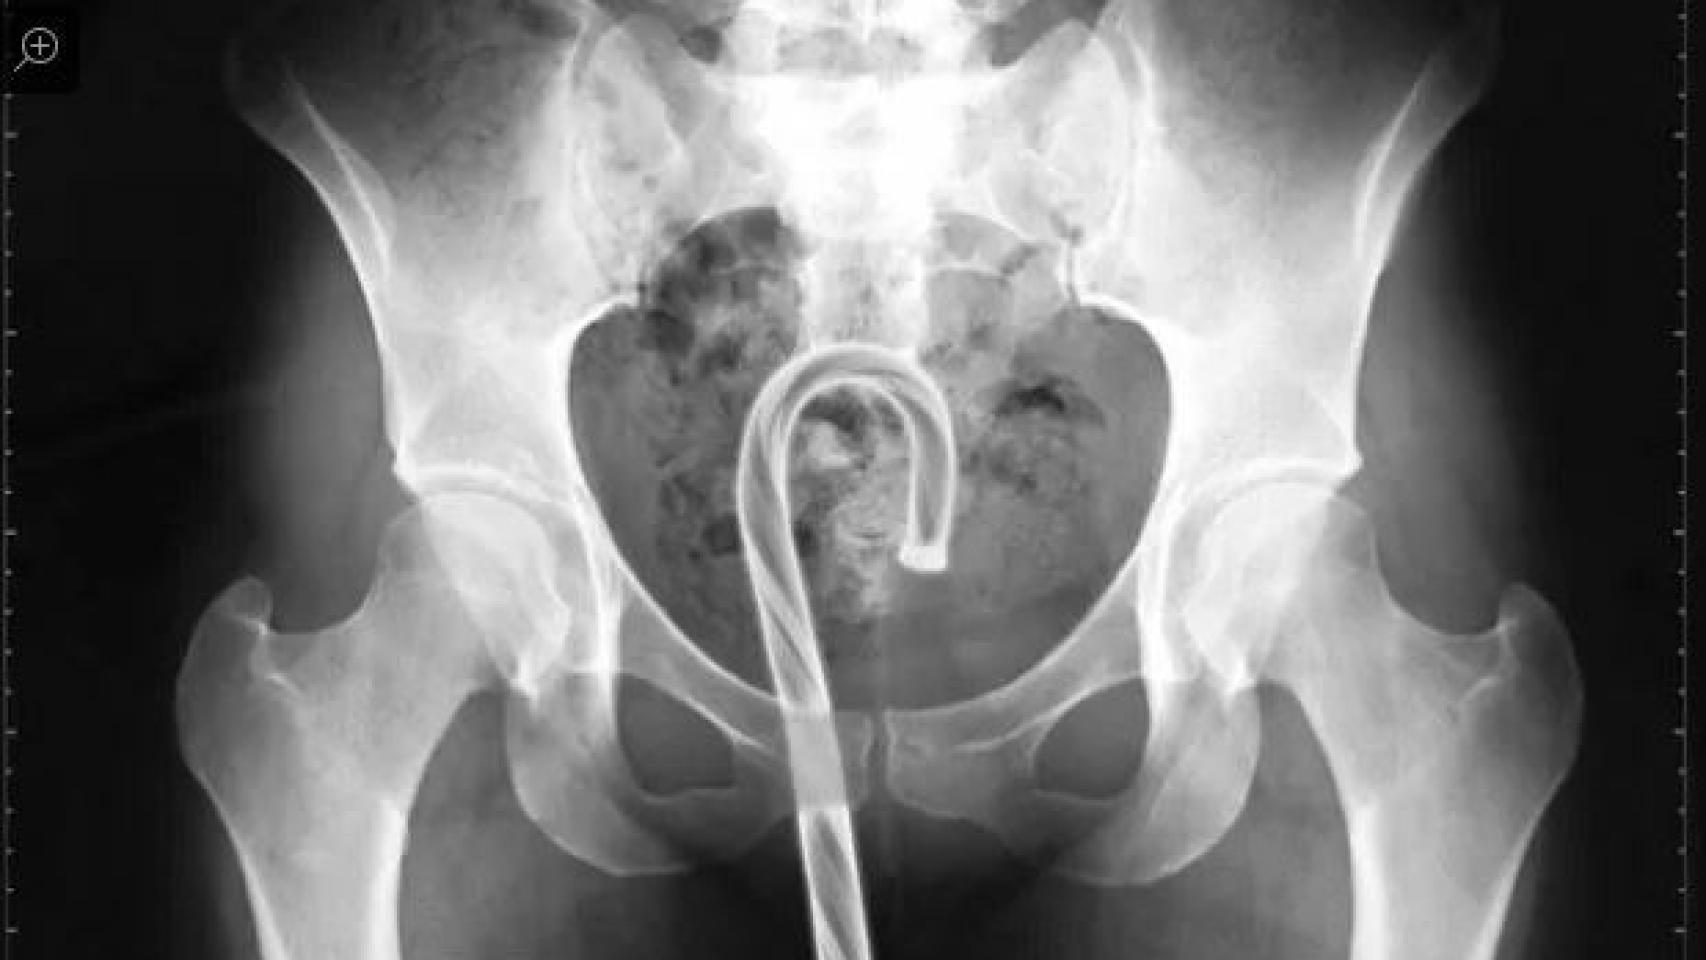

Estos son los objetos más extraños que se han encontrado en Urgencias.

La Comisión de Seguridad de Productos para el Consumidor de EEUU se limita a dar un listado de los objetos encontrados, pero no describe cómo llegaron hasta allí. Quizás no hay explicación posible para presentarse en Urgencias con un bastón de caramelo en el ano.